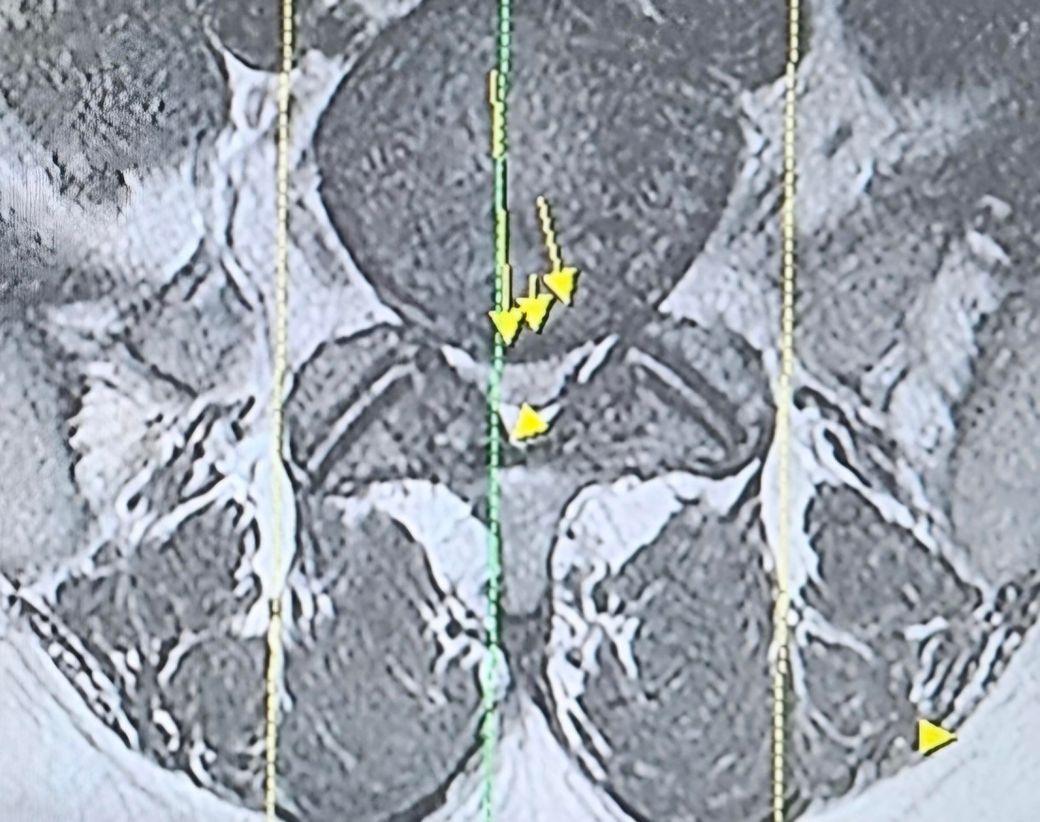

• 1번 째 사진

디스크의 섬유륜이 약간 찢어진걸로 보이고 탈출도 있는 상태인 것 같습니다.

방사통 증상이 있다는 것은 신경의 압박이 있다는 것으로 약간의 압박도 있는 것으로 보입니다.

디스크의 섬유륜이 찢어졌고 아주 가벼운 탈출이 있는 상태입니다.

신경뿌리가 눌리는건 보여주시는 영상에는 관찰되지 않습니다.

하지만 방사통이 있다는 이야기는 신경뿌리가 자극을 받고있다는 이야기입니다.